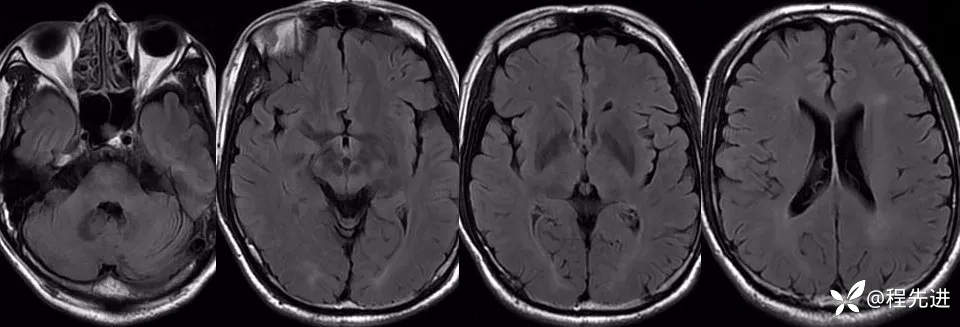

T2:

FLAIR:

影像检查: